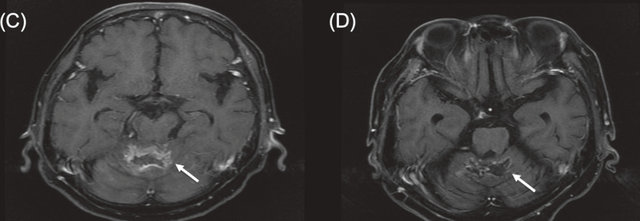

病例2

一名68岁女性,患有三阴性浸润性小叶及导管乳腺癌(左乳),出现小脑转移。她此前接受过全身化疗和立体定向放射治疗(SBRT),但出现颅内进展。BNCT治疗后MRI显示肿瘤显著消退,患者疼痛和肢体无力症状改善,未出现明显毒性反应。